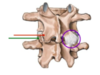

(Atlas C1)

Identifiez A

Tubercule/Arc antérieur (?)

(Atlas C1)

Identifiez B

Fossette articulaire pour la dent

(Atlas C1)

Identifiez C

Tubercule postérieur

(Atlas C1)

Identifiez D

Surface articulaire supérieur (pour le condyle occipital)

(Atlas C1)

Identifiez E

Arc postérieur

(Atlas C1)

Identifiez

Sillon de l’artère vertébrale

(Atlas C1)

Identifiez A

Face articulaire inférieure de l’atlas

(Axis C2)

Identifiez A et B

A) Odontoïde (Dent)

B) Pédicule